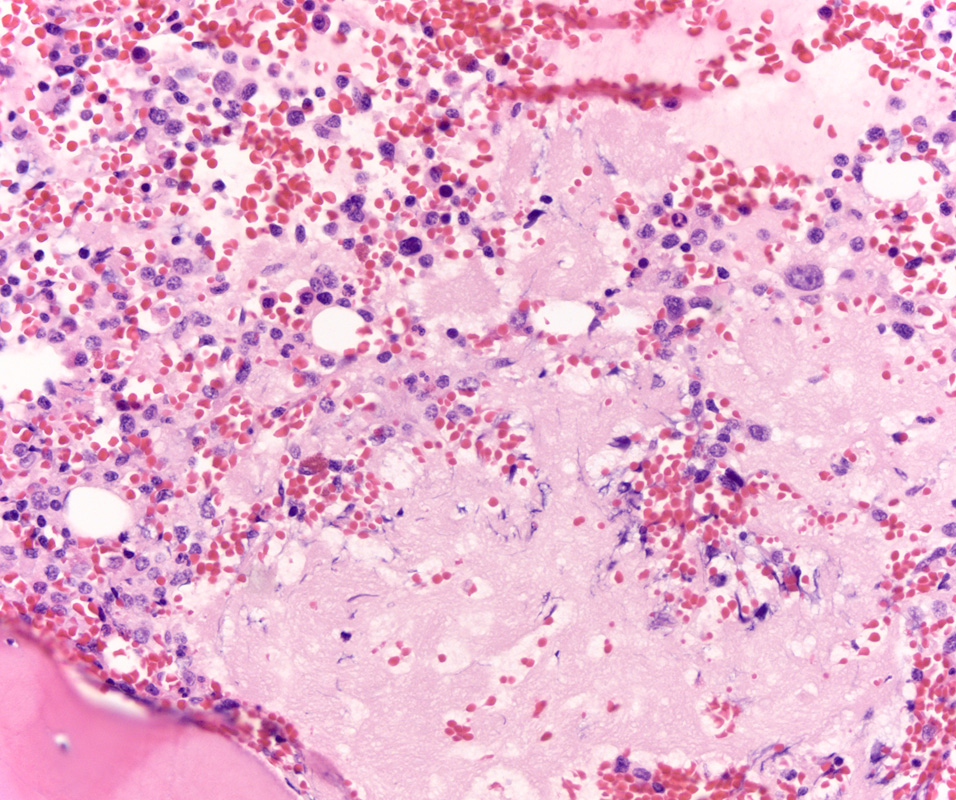

Case History

A 76-year-old male with acute renal insufficiency and a recent diagnosis of multiple myeloma...